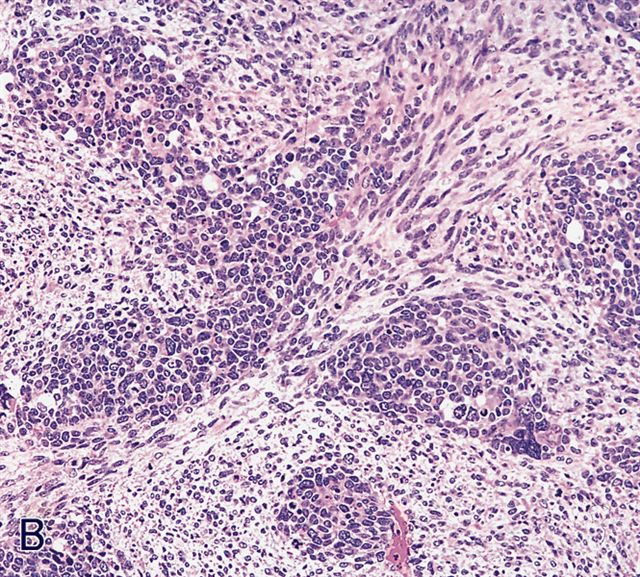

Contributed by Erdener Özer, M.D., Ph.D. and Mark R. Wick, M.D.

Contributed by Carolina Martinez Ciarpaglini, M.D., Ph.D. (Case #276) - tonsillar mass

Microscopic (histologic) description

- Composed of primitive mesenchymal cells that show variable degrees of skeletal muscle differentiation

- They are moderately cellular but in the typical pattern often contain both hypocellularity and hypercellular areas with a loose, myxoid stroma

- Perivascular condensations of tumor cells in the less cellular regions are common

- Sheets of small, stellate, spindled or round cells with scant or deeply eosinophilic cytoplasm and eccentric, small oval nuclei with a light chromatin pattern and inconspicuous nucleoli

- Botryoid variant frequently shows a cambium layer: a hypercellular zone immediately beneath the epithelial surface

- Cells are undifferentiated, round or spindled with minimal cytoplasm, frequent mitotic figures

- Deeper layers of the tumor are typically less cellular but overall conform to the histology of embryonal rhabdomyosarcoma (ERMS) with variation by region